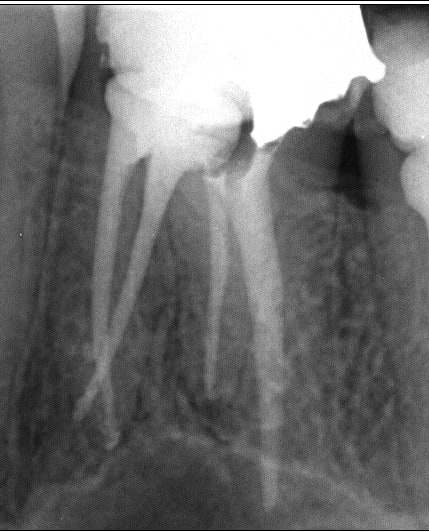

Edit 27/02/14 : J'en mets d'autres sans up. Si quelqu'un passe et que ça l'intéresse

Endo 4  1  lime cass e preop ewbdub - Eugenol

Endo 4  2  lime cass e lime pass e apsetj - Eugenol

Endo 4  3  lime cass e racine obtur e xfgnty - Eugenol

Endo 4  4  ime cass e fin nbax19 - Eugenol

Endo 5 flyu2z - Eugenol

Endo 6 exvsl8 - Eugenol